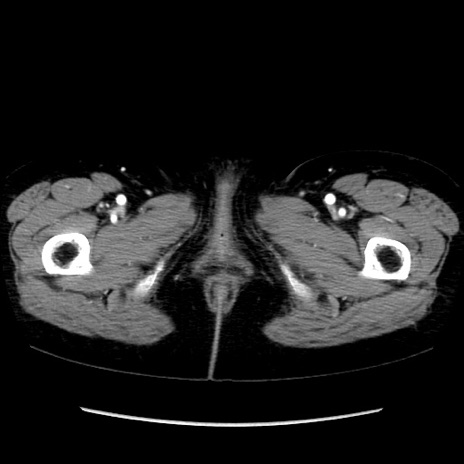

矢状断像

【症例】40歳代 女性

【主訴】上腹部痛、嘔気・嘔吐

【現病歴】約9時間前頃から急に上腹部痛、嘔気、嘔吐が出現。改善しないため救急要請。

【既往歴】子宮頚癌(広汎子宮全摘術、放射線療法)、腸閉塞

【身体所見】腹部:平坦、軟、腸雑音亢進、上腹部を中心に腹部全体に圧痛あり。

【データ】WBC 8400、CRP 0.03